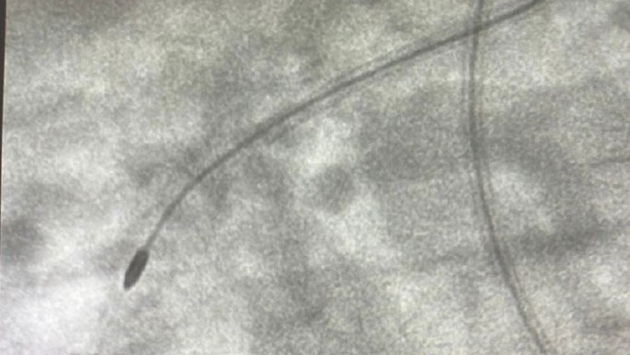

Первую процедуру ротационной атерэктомии в коронарной артерии провели врачи в Нижнем Новгороде. Операцию выполнил заведующий отделением рентгенохирургических методов Евгений Кузьменко, рассказали в НОКБ им. Семашко в соцсетях. У пациента обнаружили в артерии бляшку, которая сузила пространство на 98%. Еще немного, и это бы привело к инфаркту из-за непроходимости эритроцитов и других компонентов крови. Чтобы восстановить кровообращение, не было возможности даже поставить стент из-за оставшегося узкого прохода в артерии. Тогда в процедуру решили включить специальное устройство рентгенохирургов — специальный маленький бур, похожий на оливку и вращающийся со скоростью до 180 тысяч оборотов в минуту. С помощью него и удалили атеросклеротическую бляшку, а затем при помощи стента и восстановили нормальный просвет артерии. Ранее на сайте pravda-nn.ru сообщалось, что мужчину с червем-паразитом в печени спасли кстовские врачи.